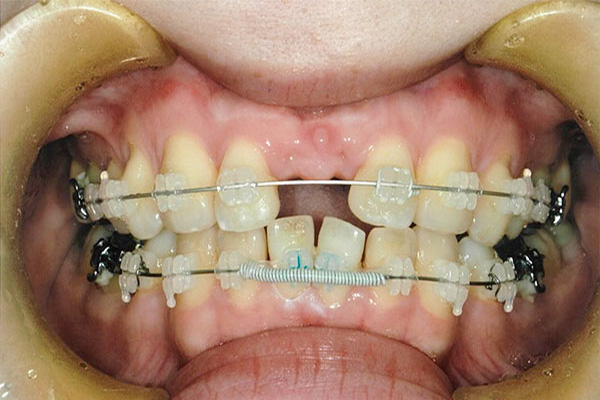

1年6ヶ月後